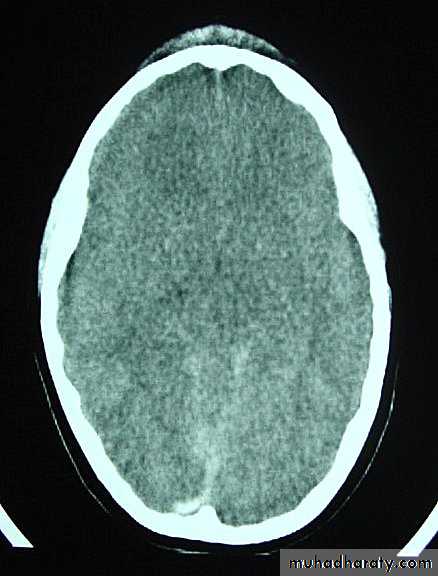

1. Brain Oedema (Cerebral Swelling)

Can be local (around a haematoma) or diffuse.

It is due to intracellular or extracellular accumulation of fluid.

It leads to raised intracranial pressure, which itself causes problems.

It is more common and more dangerous in children.